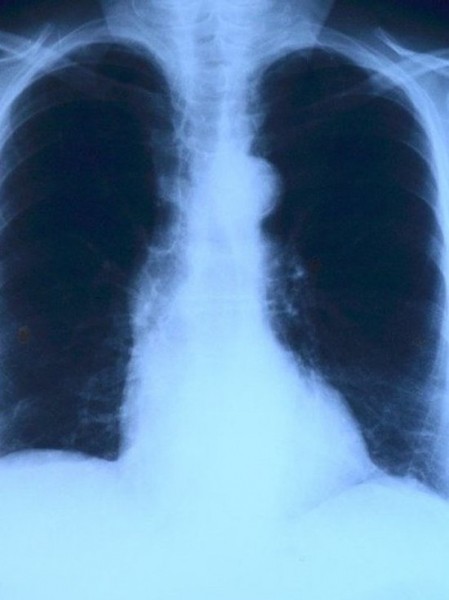

За последний год число внебольничных пневмоний в Татарстане выросло вдвое. Такие данные на расширенном заседании коллегии Минздрава РТ привела глава Управления Роспотребнадзора по РТ Марина Патяшина.

По ее словам, рост числа заболеваемости связан с введением диагностики методом РКТ. Рост числа внебольничных заболеваний органов дыхания отмечается повсеместно по РФ, отметила она.

Кроме того, из-за широкого применения КТ с конца весны отмечается высокая доля пневмоний с легким течением. По сравнению с 2019 годом их число выросло в четыре раза, заключила глава Управления.